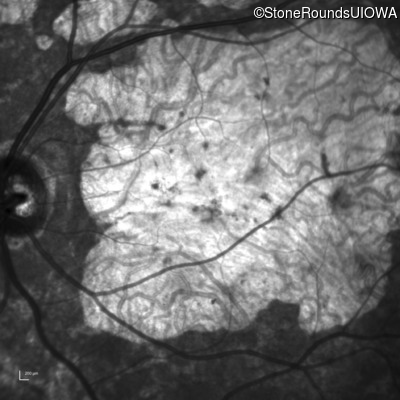

| AR Stargardt Disease | ABCA4 | Cys205Phe TGC>TTC | Gly863Ala (G)GA>(G)CA | AR |